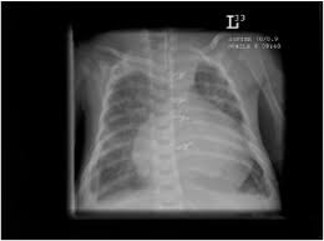

Cardiac tamponade

This complication may occur if the tip of the PICC line lies within the heart. To avoid this complication the tip of all PICC lines must be seen clearly outside of the cardiac silhouette. See advice on imaging above. Cases have been recorded where the tip appears to have migrated after the initial X-ray. To guard against this, the tip of the line should be noted on any subsequent x-ray taken for other reasons. The following symptoms and signs may alert the clinician that tamponade has occurred

- Enlarged cardiac shadow on x-ray

Cardiac tamponade can be easily diagnosed using an ultrasound scanner as there will be a large collection of fluid around the heart. See appendix for the procedure for aspiration of a cardiac tamponade.

![]() |

Cardiac tamponade is a rare complication of PICC line use in neonatal units. It is a medical emergency, with associated morbidity and mortality. Literature suggests an incidence of 0.76% to 3% in infants with PICC lines. Retrospective data from the UK estimate an incidence of 0.2%, with a mortality of 0.7 per 1000 neonates. Initial resuscitation should be methodical and follow recognised life support guidelines. Siting catheter tips outwith the cardiac border does not completely abolish the risk of pericardial effusion, or cardiac tamponade.12

- Chest X-ray: Widened mediastinum +/- fluid level

- ECHO (if available/ time permits)